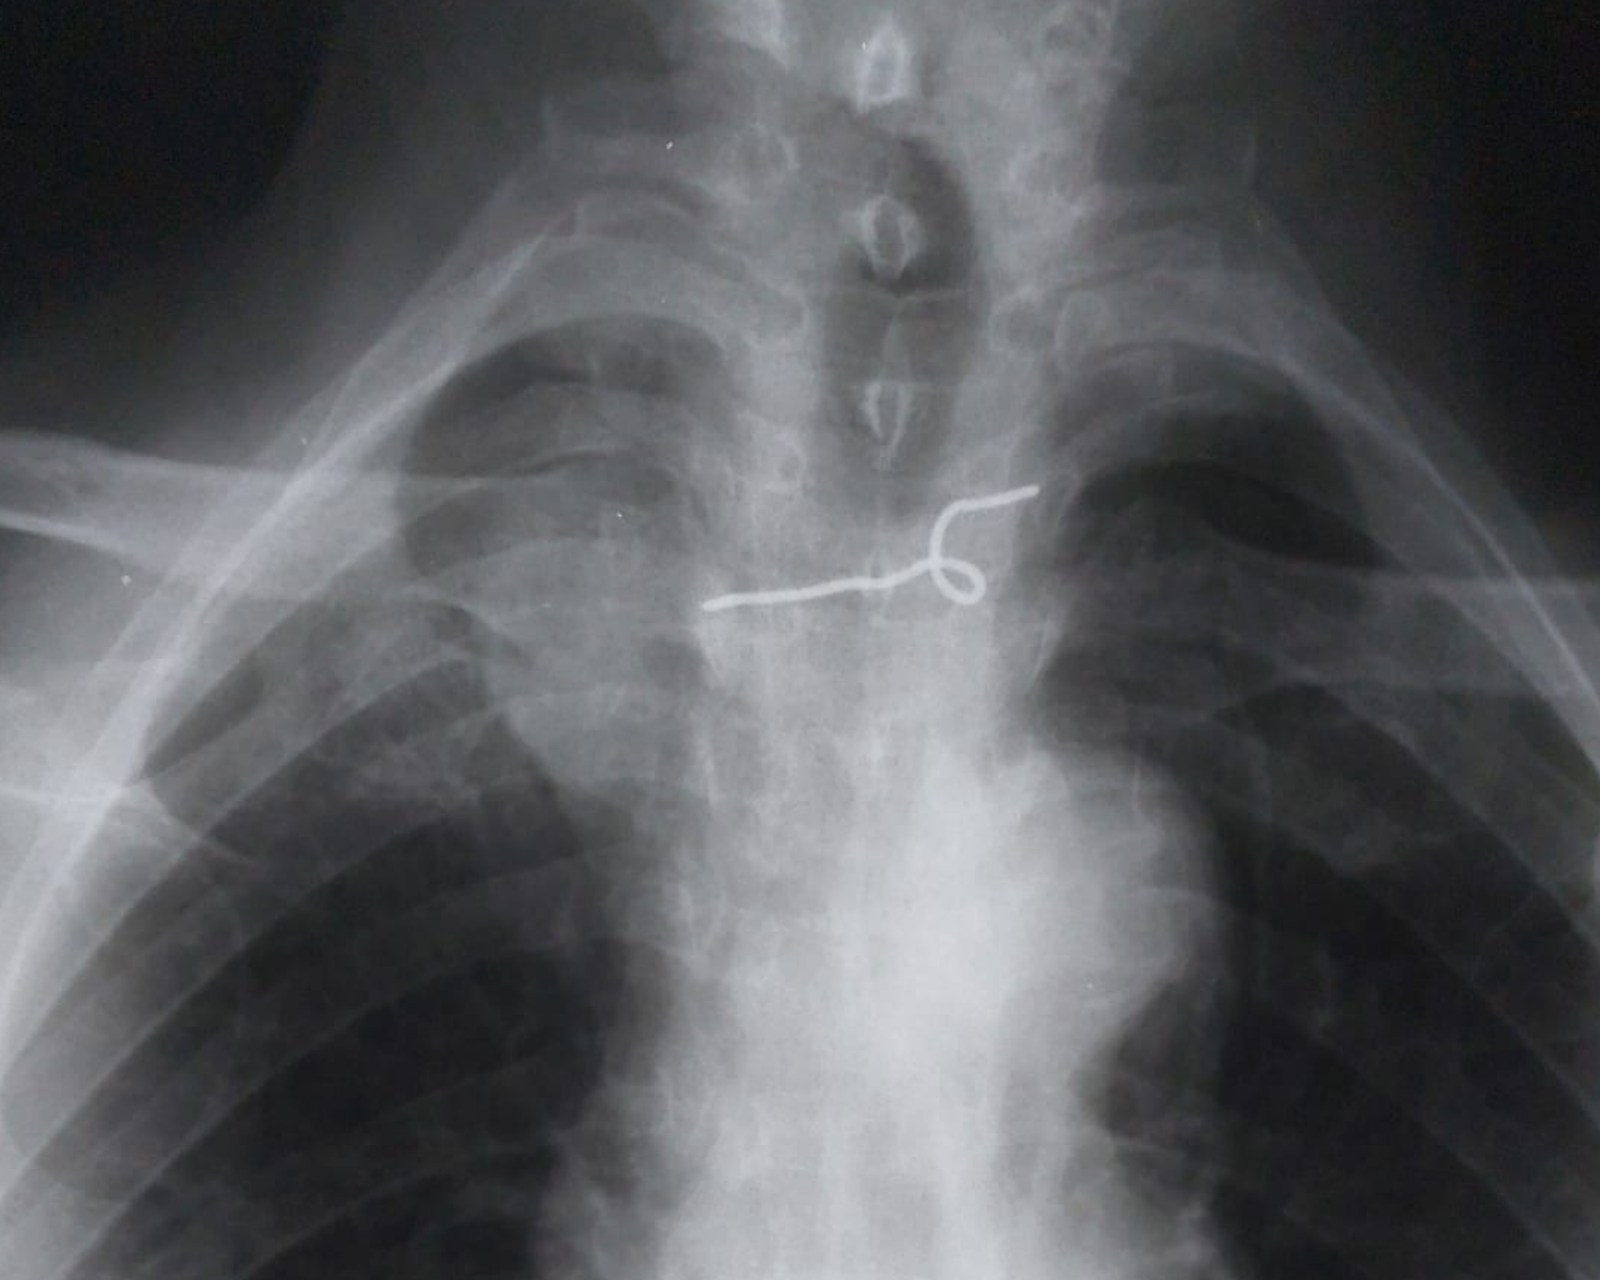

Uma idosa de 67 anos, deu entrada no Hospital Municipal Áurea Maia de Figueiredo, em São Miguel do Alto Oeste (RN), após ingerir um corpo estranho que só foi identificado após realização de um raio-x. Inicialmente os médicos suspeitavam que era um pedaço de osso, mas, na verdade, dona Lindalva Leite da Silva, teria engolido um pedaço de metal, mais parecido com um arame.

Segundo o enfermeiro que atendeu a senhora quando ela deu entrada no hospital de São Miguel, a paciente queixava-se de leve dor na garganta e esôfago. “Achamos que ela teria ingerido um pedaço de osso inicialmente, diante dessa informação, passei para o médico e ele solicitou um raio-x, e quando ela fez o exame, a imagem que tínhamos era realmente de um pedaço de metal, mais parecido com um arame, após isso, ela foi encaminhada para o hospital regional de Pau dos Ferros”, contou o profissional da saúde.

Lindalva teria engolido o pedaço de metal quando estava comendo farinha, os detalhes ainda não foram revelados, mas, a família alega não saber como o arame foi parar na comida da idosa.